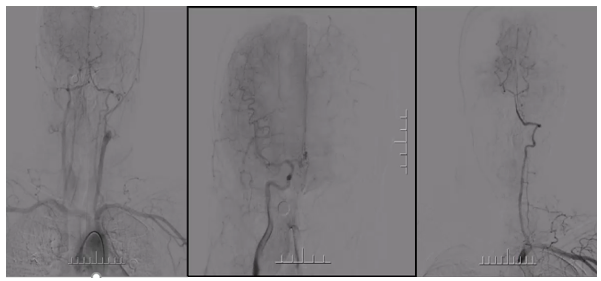

手术方案

病历夹什么径技·第151期|串联营病历夹:京广连营_https://www.jmylbn.com_新闻资讯_第75张

病历夹什么径技·第151期|串联营病历夹:京广连营_https://www.jmylbn.com_新闻资讯_第76张

病历夹什么径技·第151期|串联营病历夹:京广连营_https://www.jmylbn.com_新闻资讯_第77张

<<滑动查看下一张图片>>

• 左侧椎动脉造影见基底动脉起始处闭塞。

• 微导管造影,见基底动脉尖及左侧大脑后动脉显影不良,考虑栓塞。

• 基底动脉近端打开支架,支架形态尚可,局部发白,左侧大脑前动脉P1段栓塞。

• 支架取栓取出一小块栓子,造影见基底动脉起始处重度狭窄。

• 狭窄处予球囊扩张成形,球扩后造影见基底动脉狭窄有所改善。

• 微导管送至左侧大脑后动脉P2段,造影确认真腔后,释放支架,并支架取栓1次。

• 血栓成功取出,基底动脉侧位造影,左侧大脑后动脉再通。

• 正位造影,左侧大脑后动脉再通,无血栓逃逸,基底动脉狭窄改善,未回缩,前向血流正常,观察后结束手术。